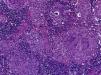

El hallazgo histológico característico de la sarcoidosis es la presencia de granulomas epitelioides no caseificantes esparcidos de manera difusa en diferentes tejidos, pero que principalmente afectan al ganglio linfático.

Los granulomas de la sarcoidosis tienen aspecto compacto, con límites bien definidos. Pueden encontrarse en distintas etapas de evolución, que van desde granulomas altamente celulares hasta lesiones con celularidad disminuida, con fibrosis o con hialinización progresiva; además, no presentan necrosis central ni evidencia de cuerpos extraños, lo cual permite diferenciarlos de los granulomas observados en infecciones por micobacterias, micosis sistémicas e infestaciones por metazoarios.

La zona central o folículo, constituida por un denso conglomerado de células epitelioides en forma de racimos, acompañados de linfocitos, macrófagos, células gigantes multinucleadas de Langhans, mastocitos y fibroblastos. En el 60% de los casos se observan estructuras de aspecto estelar (o cuerpos asteroides) y estructuras laminares llamadas cuerpos de Schaumann, de 1-15μm de diámetro y PAS+. En estudios con métodos inmunohistoquímicos, la zona central de un granuloma activo consiste en macrófagos en diversas etapas de activación y diferenciación. Esta zona está rodeada por células T CD4+ intercaladas con un pequeño número de células T CD8+ y células B.

La zona periférica, formada por un anillo de linfocitos, monocitos y fibroblastos. En la periferia del granuloma se acumulan las células T reguladoras CD3+/CD4+/CD25+/ +Fox P3, además de células T CD8+ y fibroblastos, que cuando disminuye la actividad de los granulomas, producen la fibrosis.

En la forma crónica de la enfermedad, los granulomas pueden estar encapsulados por un halo fibroso o pueden ser sustituidos por cicatrices de tejido fibroso y hialino32–34.

Se realizó la biopsia de ganglio supraclavicular con tinciones de hematoxilina/eosina, Grocott, Ziehl-Neelsen y PAS. Los cortes histológicos mostraron ganglios linfáticos con pérdida de la arquitectura, secundaria a la formación de múltiples granulomas no caseificantes confluentes entre sí (fig. 7), constituidos por numerosos macrófagos epitelioides, células gigantes tipo Langhans y otras tipo cuerpo extraño. Se observaron, de forma ocasional, calcificaciones concéntricas o cuerpos de Schaumann (fig. 8) y formas compatibles con cuerpos asteroideos (fig. 9). Con las tinciones especiales no se observaron microorganismos, y las pruebas de PCR así como los cultivos en tejido del ganglio para Mycobacterium tuberculosis fueron negativos. Diagnóstico histopatológico: ganglios linfáticos supraclaviculares con linfadenitis crónica granulomatosa no caseificante concordante con sarcoidosis.